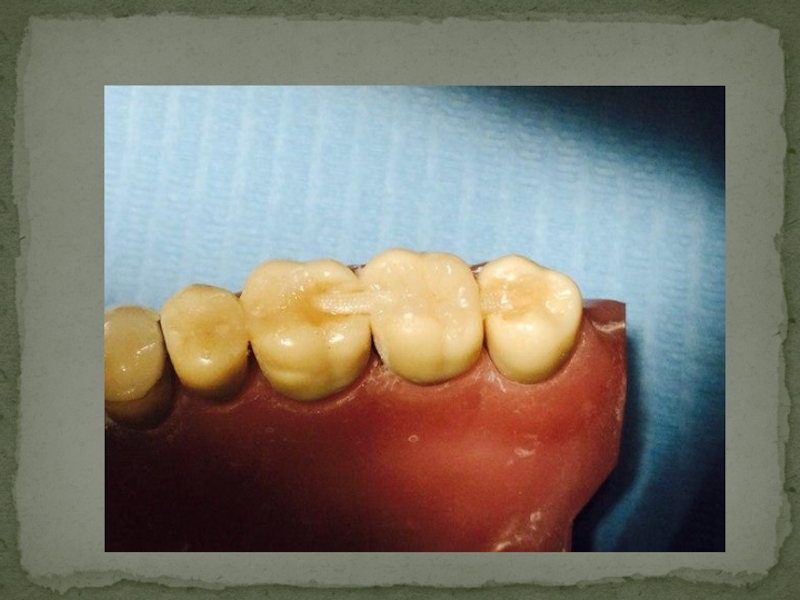

Слайд 11ШИНИРОВАНИЕ БОКОВЫХ ЗУБОВ

ШИНИРОВАНИЕ БОКОВЫХ ЗУБОВ